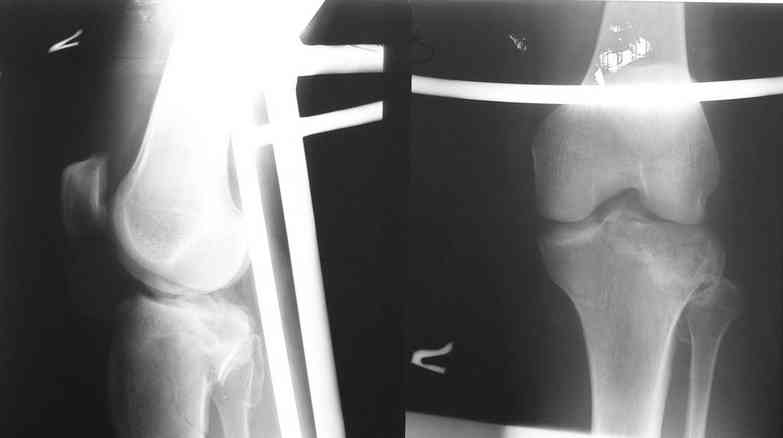

Re: Мыщелки голени

Спасибо за ответ высылаю R- граммы пациента. Ранее как и в это раз оперировали открыто репонируя суставную поверхность из дополнительного окна по передней поверхности мыщелка дефект губчатой ткани заполняли аутотрансплантатом с гребня подвздошной кости или пористым никелид титаном и фиксировали мыщелковой пластиной. В данном случае межмыщелковое возвышение фиксировали проволочным швом окно для поднятия суставной поверхности сформировали по передне-наружной поверхности н/мыщелка, дефект заполнили аутокостью и фиксировали пластиной с угловой стабильностью с болтом-стяжкой. В ближайшие дни покажу контроль R-гр, КТ.